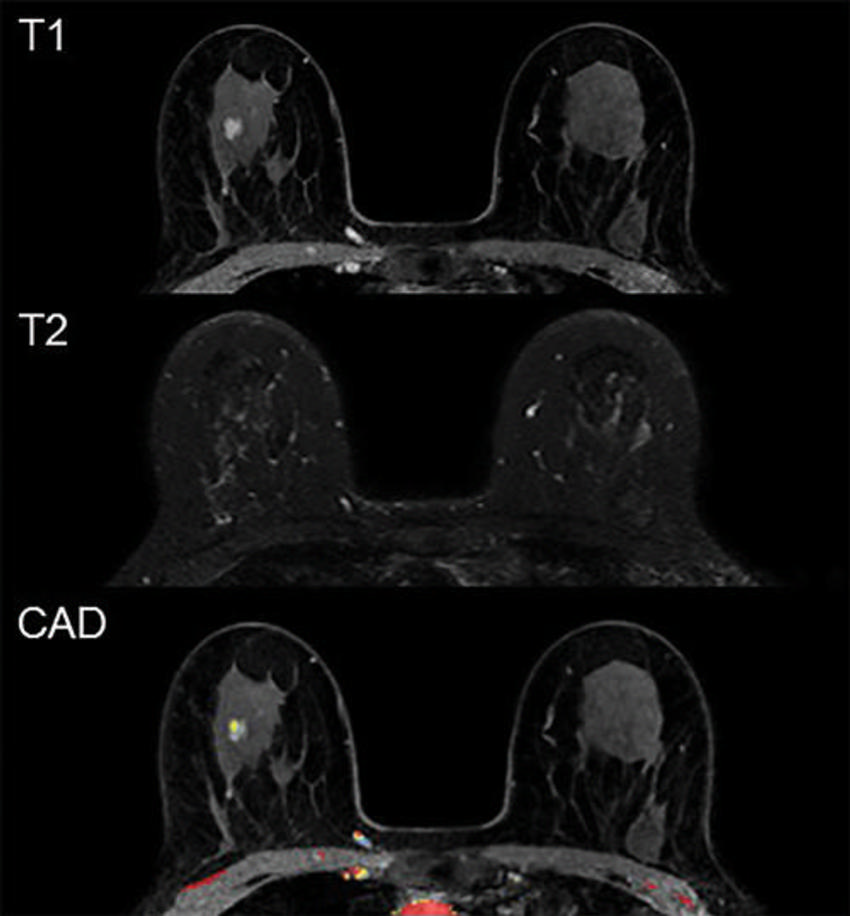

Figure 1. Example of a false-positive MRI. In a 59-year-old participant, first-round screening MRI showed an 8-mm irregular mass in the right breast. The lesion shows rapid heterogeneous type 2 enhancement, low T2 signal intensity, and no evident diffusion restriction. Histopathologic findings showed sclerotic stroma and apocrine metaplasia.